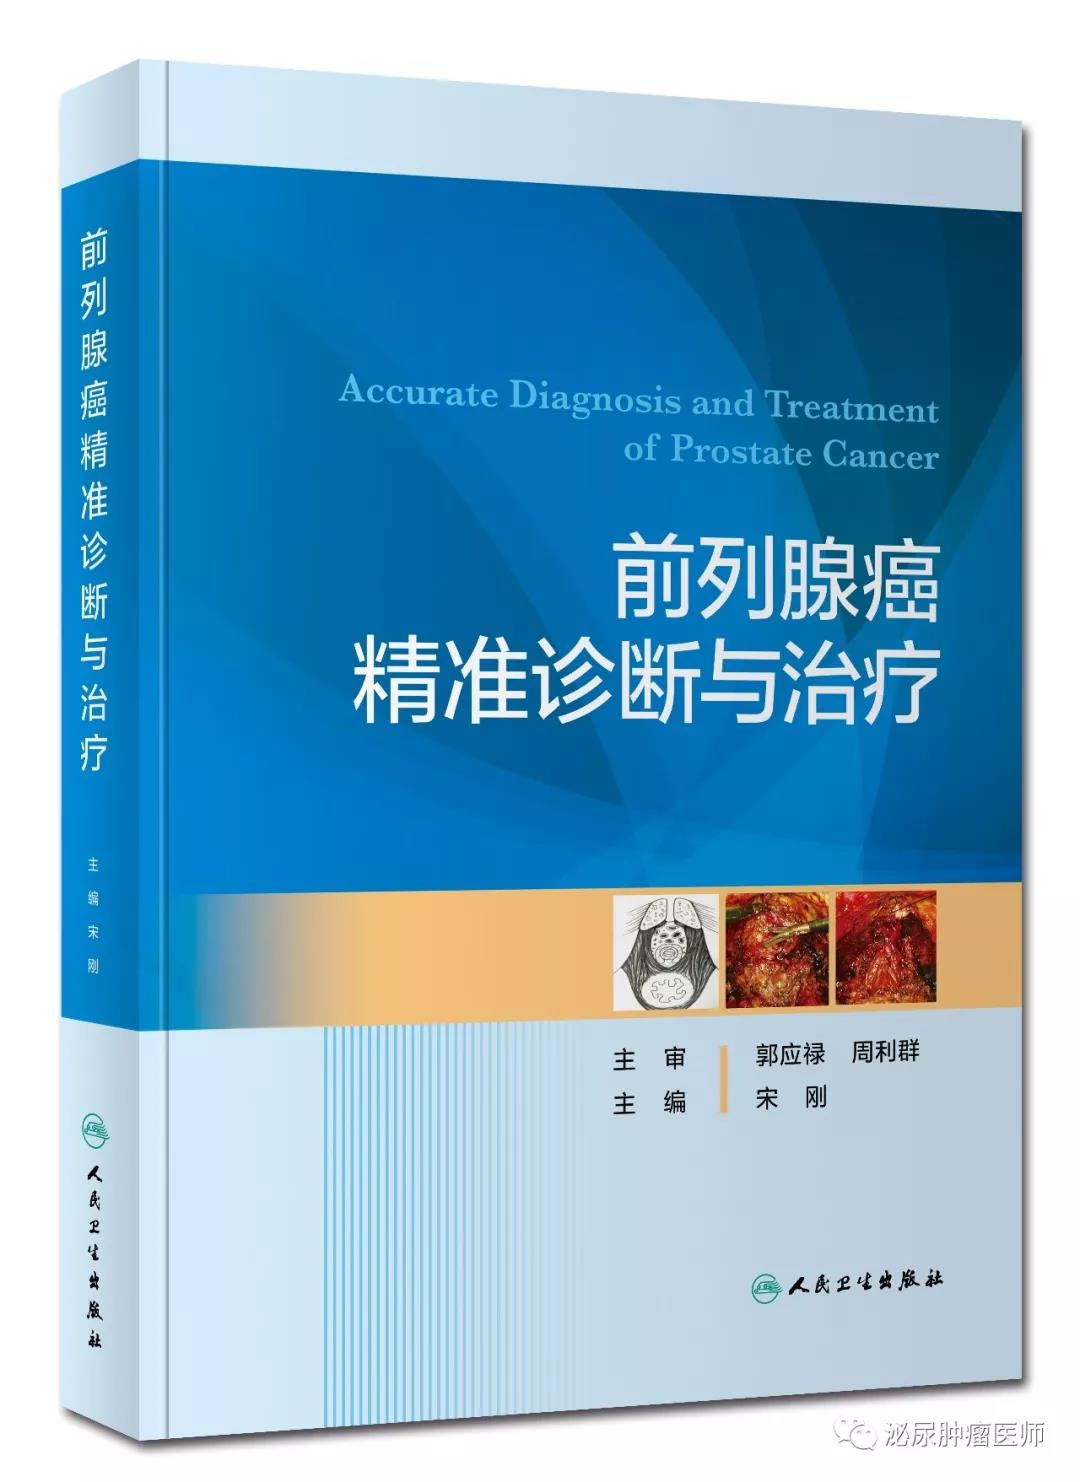

近日,国内外肿瘤治疗迎来了8项新药或新适应证,一起来跟进肿瘤药物这些新资讯。国内上市新药或新适应证8月14日,国内首个自主开发的曲妥珠单抗获得国家药品监督管理局(...